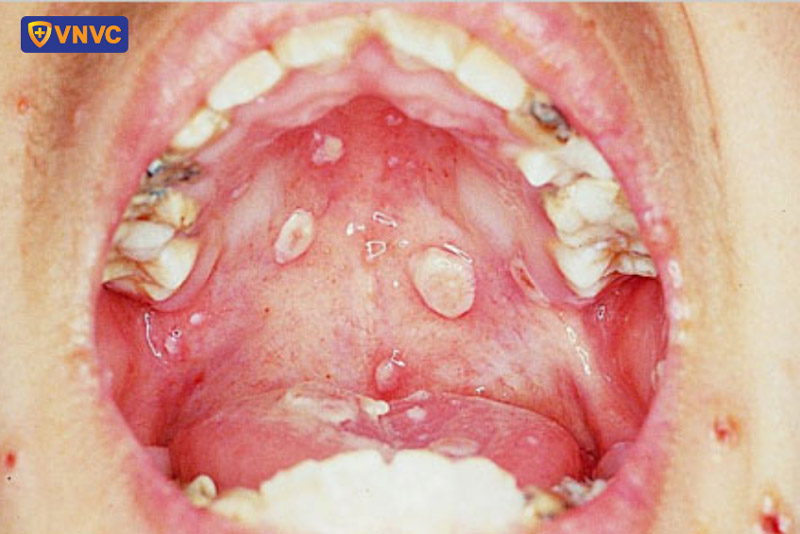

Hình ảnh phân biệt thủy đậu và zona thần kinh qua từng giai đoạn bệnh

1.2. Hình ảnh thủy đậu giai đoạn 2

Ở giai đoạn tiếp theo, các nốt ban phát triển thành mụn nước chứa dịch trong. Theo thời gian, các nốt mụn tích tụ nhiều mủ hơn, căng hơn, mủ vàng hoặc đục, dễ vỡ hơn và lõm nhẹ ở đỉnh các đầu mụn.